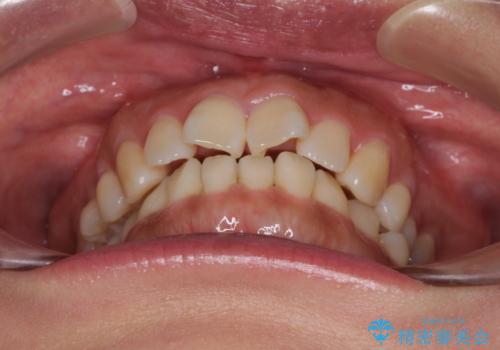

- 上下前歯の叢生を気にして来院された患者様です。

費用を抑え、期間もあまりかけずに治療をしたいとのことで、インビザライン・ライトを用いて矯正治療を行うこととしました。